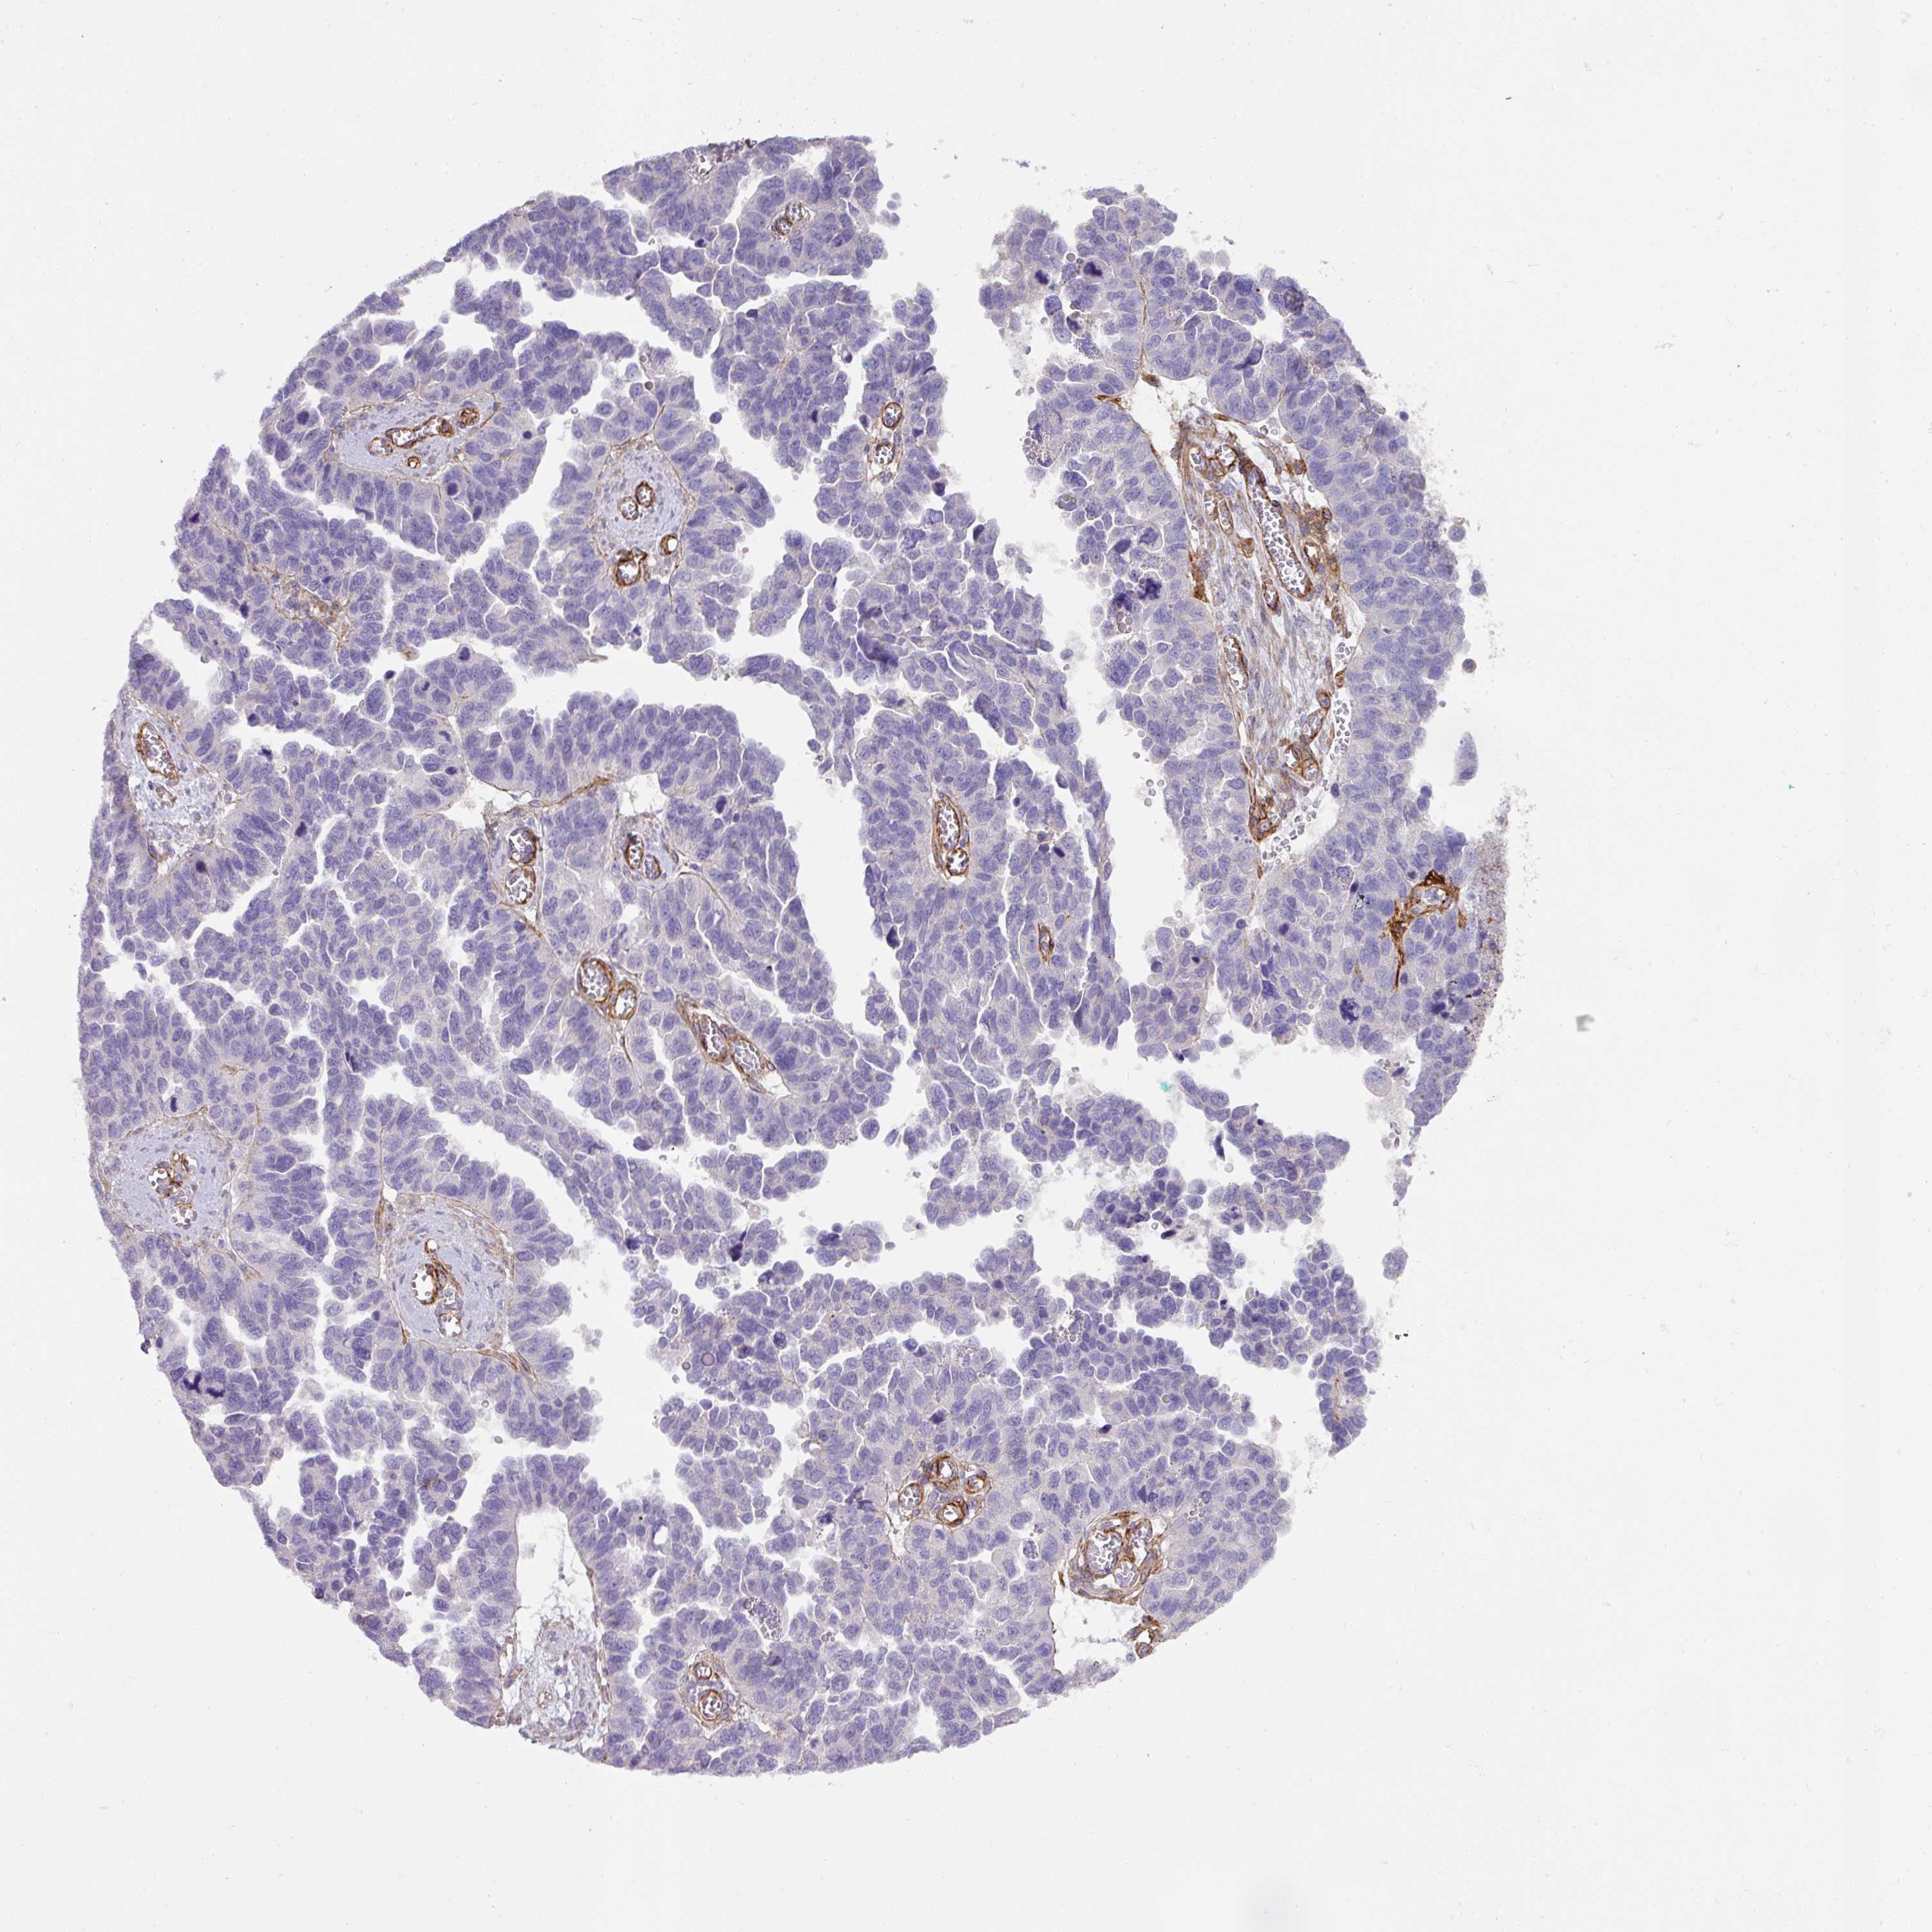

OVARIAN CANCER - Protein expressioni

A mouse-over function shows sample information and annotation data. Click on an image to view it in a full screen mode. Samples can be filtered based on level of antibody staining by selecting one or several of the following categories: high, medium, low and not detected. The assay and annotation is described here.

Note that samples used for immunohistochemistry by the Human Protein Atlas do not correspond to samples in the TCGA dataset.

Antibody stainingi

Antibody staining in the annotated cell types in the current human tissue is reported as not detected, low, medium, or high, based on conventional immunohistochemistry profiling in selected tissues. This score is based on the combination of the staining intensity and fraction of stained cells.

Each image is clickable and will lead to virtual microscopy that enables deeper exploration of all samples and also displays staining intensity scores, fraction scores and subcellular localization as well as patient and tissue information for each sample.

Antibody HPA052708

Staining

High

Medium

Low

Not detected

Intensity

Strong

Moderate

Weak

Negative

Quantity

>75%

75%-25%

<25%

None

Location

Nuclear

Cytoplasmic/membranous

Cytoplasmic/membranous,nuclear

Cystadenocarcinoma, serous, NOS

Cystadenocarcinoma, mucinous, NOS

Adenocarcinoma, NOS

Carcinoma, endometroid